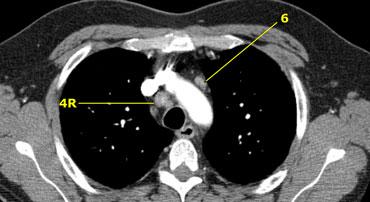

Bên trái là hạch cạnh khí quản 4R.

Ngoài ra còn có một hạch động mạch chủ nằm bên ngoài quai động mạch chủ, tức là hạch nhóm 6.

6. Cạnh động mạch chủ

Đây là các hạch của động mạch chủ lên hoặc hạch cơ hoành, nằm ở phía trước và bên của động mạch chủ lên và quai động mạch chủ.

6. Hạch cạnh động mạch chủ

Hạch cạnh động mạch chủ (động mạch chủ lên hoặc cơ hoành) nằm ở phía trước và bên ngoài động mạch chủ lên và quai động mạch chủ, từ bờ trên đến bờ dưới của quai động mạch chủ.